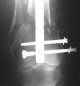

Attached are few examples from our Hospital:

Malpositioning is much too common (recurvatum, varus - valgus).

B. Fixation loosening: distal cutting of the nail, non-unions do happen (cases attached).